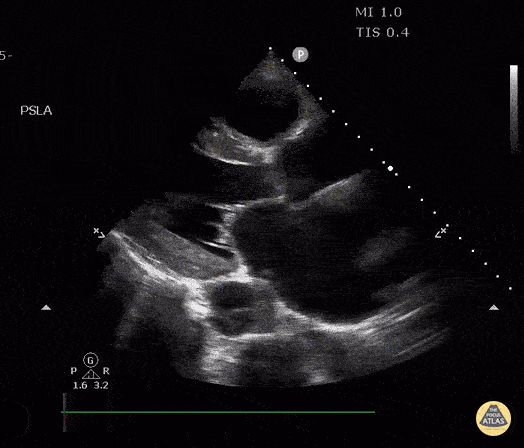

Thoracic Aortic Dissection & Aneurysm - Descending Thoracic Aortic Dissection Seen on PSLA

This is a parasternal long axis view of an elderly male with PMH of hypertension and DM presenting with a dissection of the descending aorta (aka type B aortic dissection). Image courtesy of Robert Jones, DO, FACEP @RJonesSonoEM Director, Emergency Ultrasound; MetroHealth Medical Center; Professor, Case Western Reserve Medical School, Cleveland, OH Find his original post here